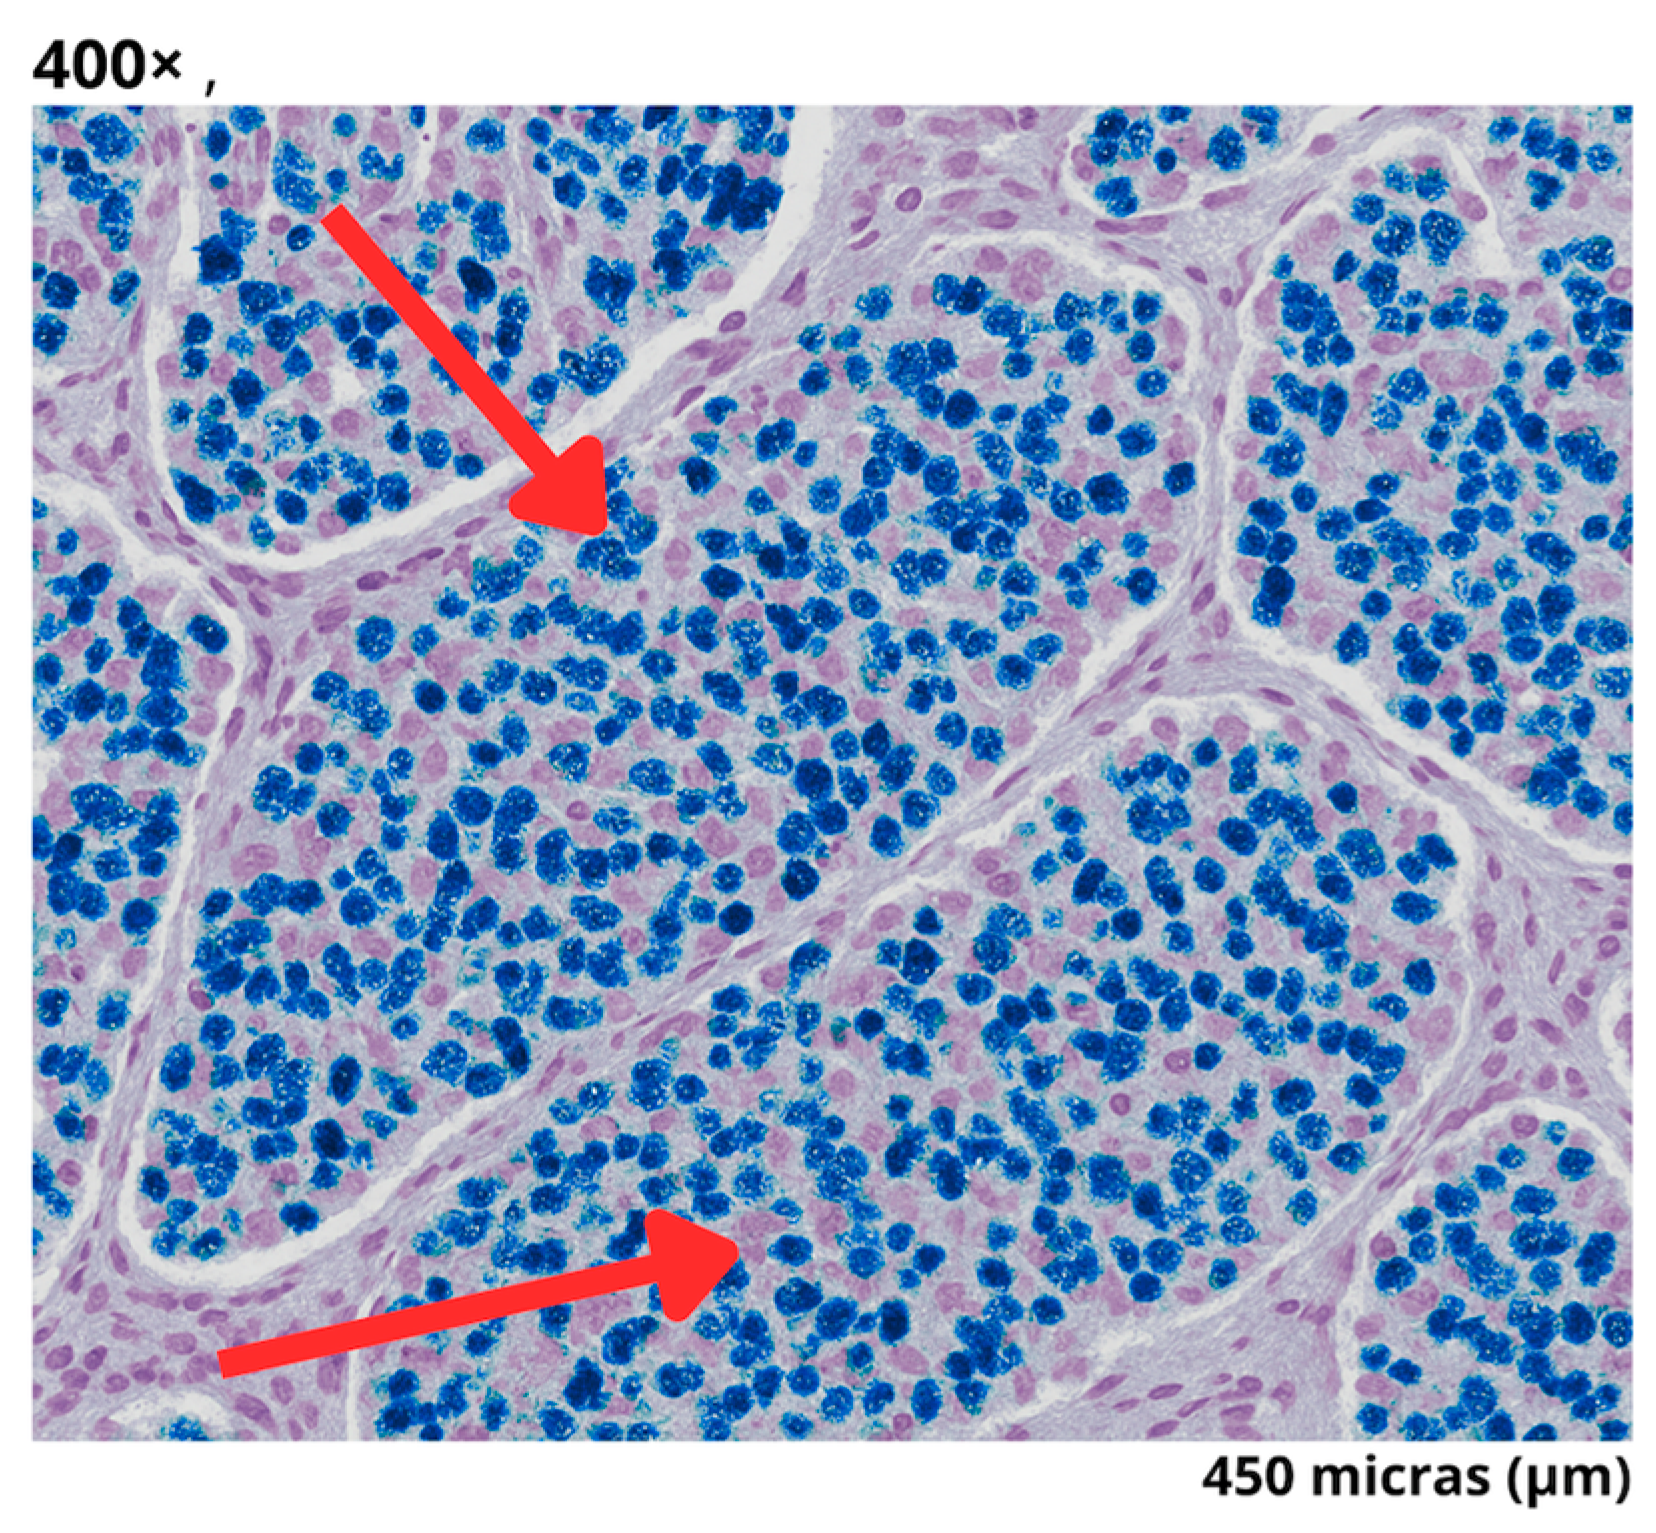

2.4. Surgical Intervention and Intraoperative Findings

| Biopsy Type | Findings |

|---|---|

| Frozen Section | Compatible with neuroendocrine tumor |

| Pathology | Well-differentiated grade 3 neuroendocrine tumor (2.5 × 1.5 × 1 cm) |

| Immunohistochemistry/Histology | Well-differentiated neuroendocrine tumor, (2 mitoses per 2 mm2) with a Ki-67 proliferation index of 21% |